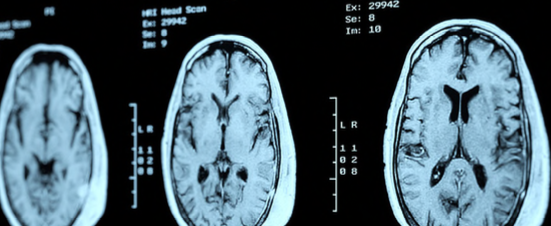

Promoting Brain Health and Brain Fitness: A National Call to Action